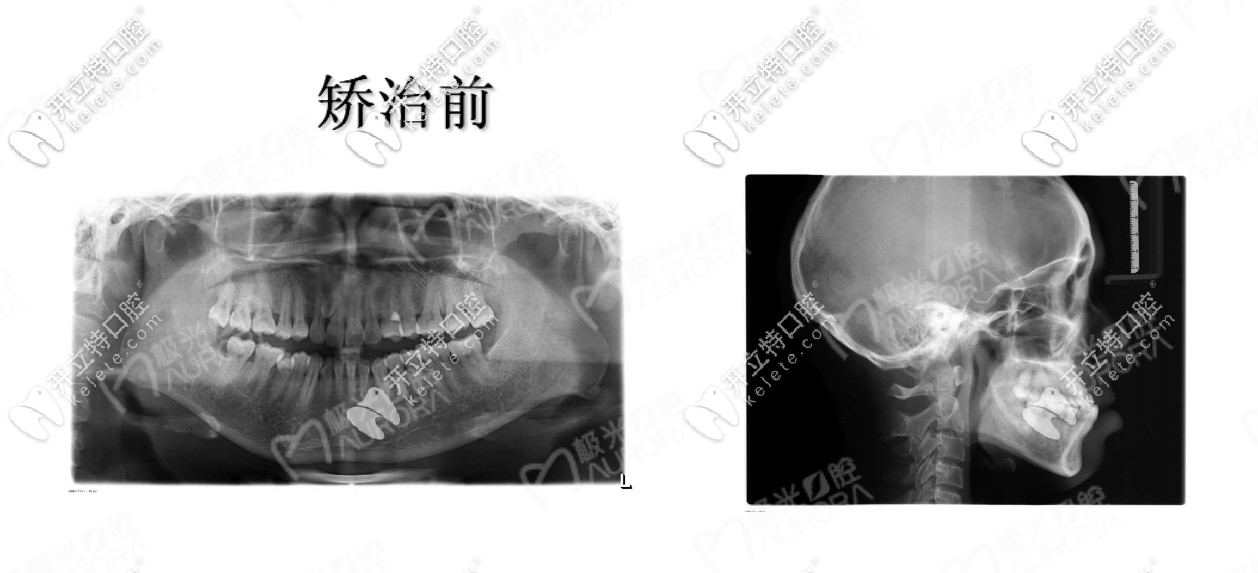

醫(yī)助結合我的需求給我介紹的醫(yī)生也很有耐心,拍片檢查后看我雖然是地包天,但是我的牙周情況良好屬于牙性因素的反合。

牙片真是個好東西,我終于全面看到了自己牙齒,說實話,有點嫌棄啊,醫(yī)生給我介紹的隱形矯正和鋼絲矯正,但是為了美觀和方便,我選擇的是隱適美隱形牙套,因為隱適美會對推磨牙后移的矯正速度減少,具體醫(yī)生咋說的,我給忘啦!嗚嗚!